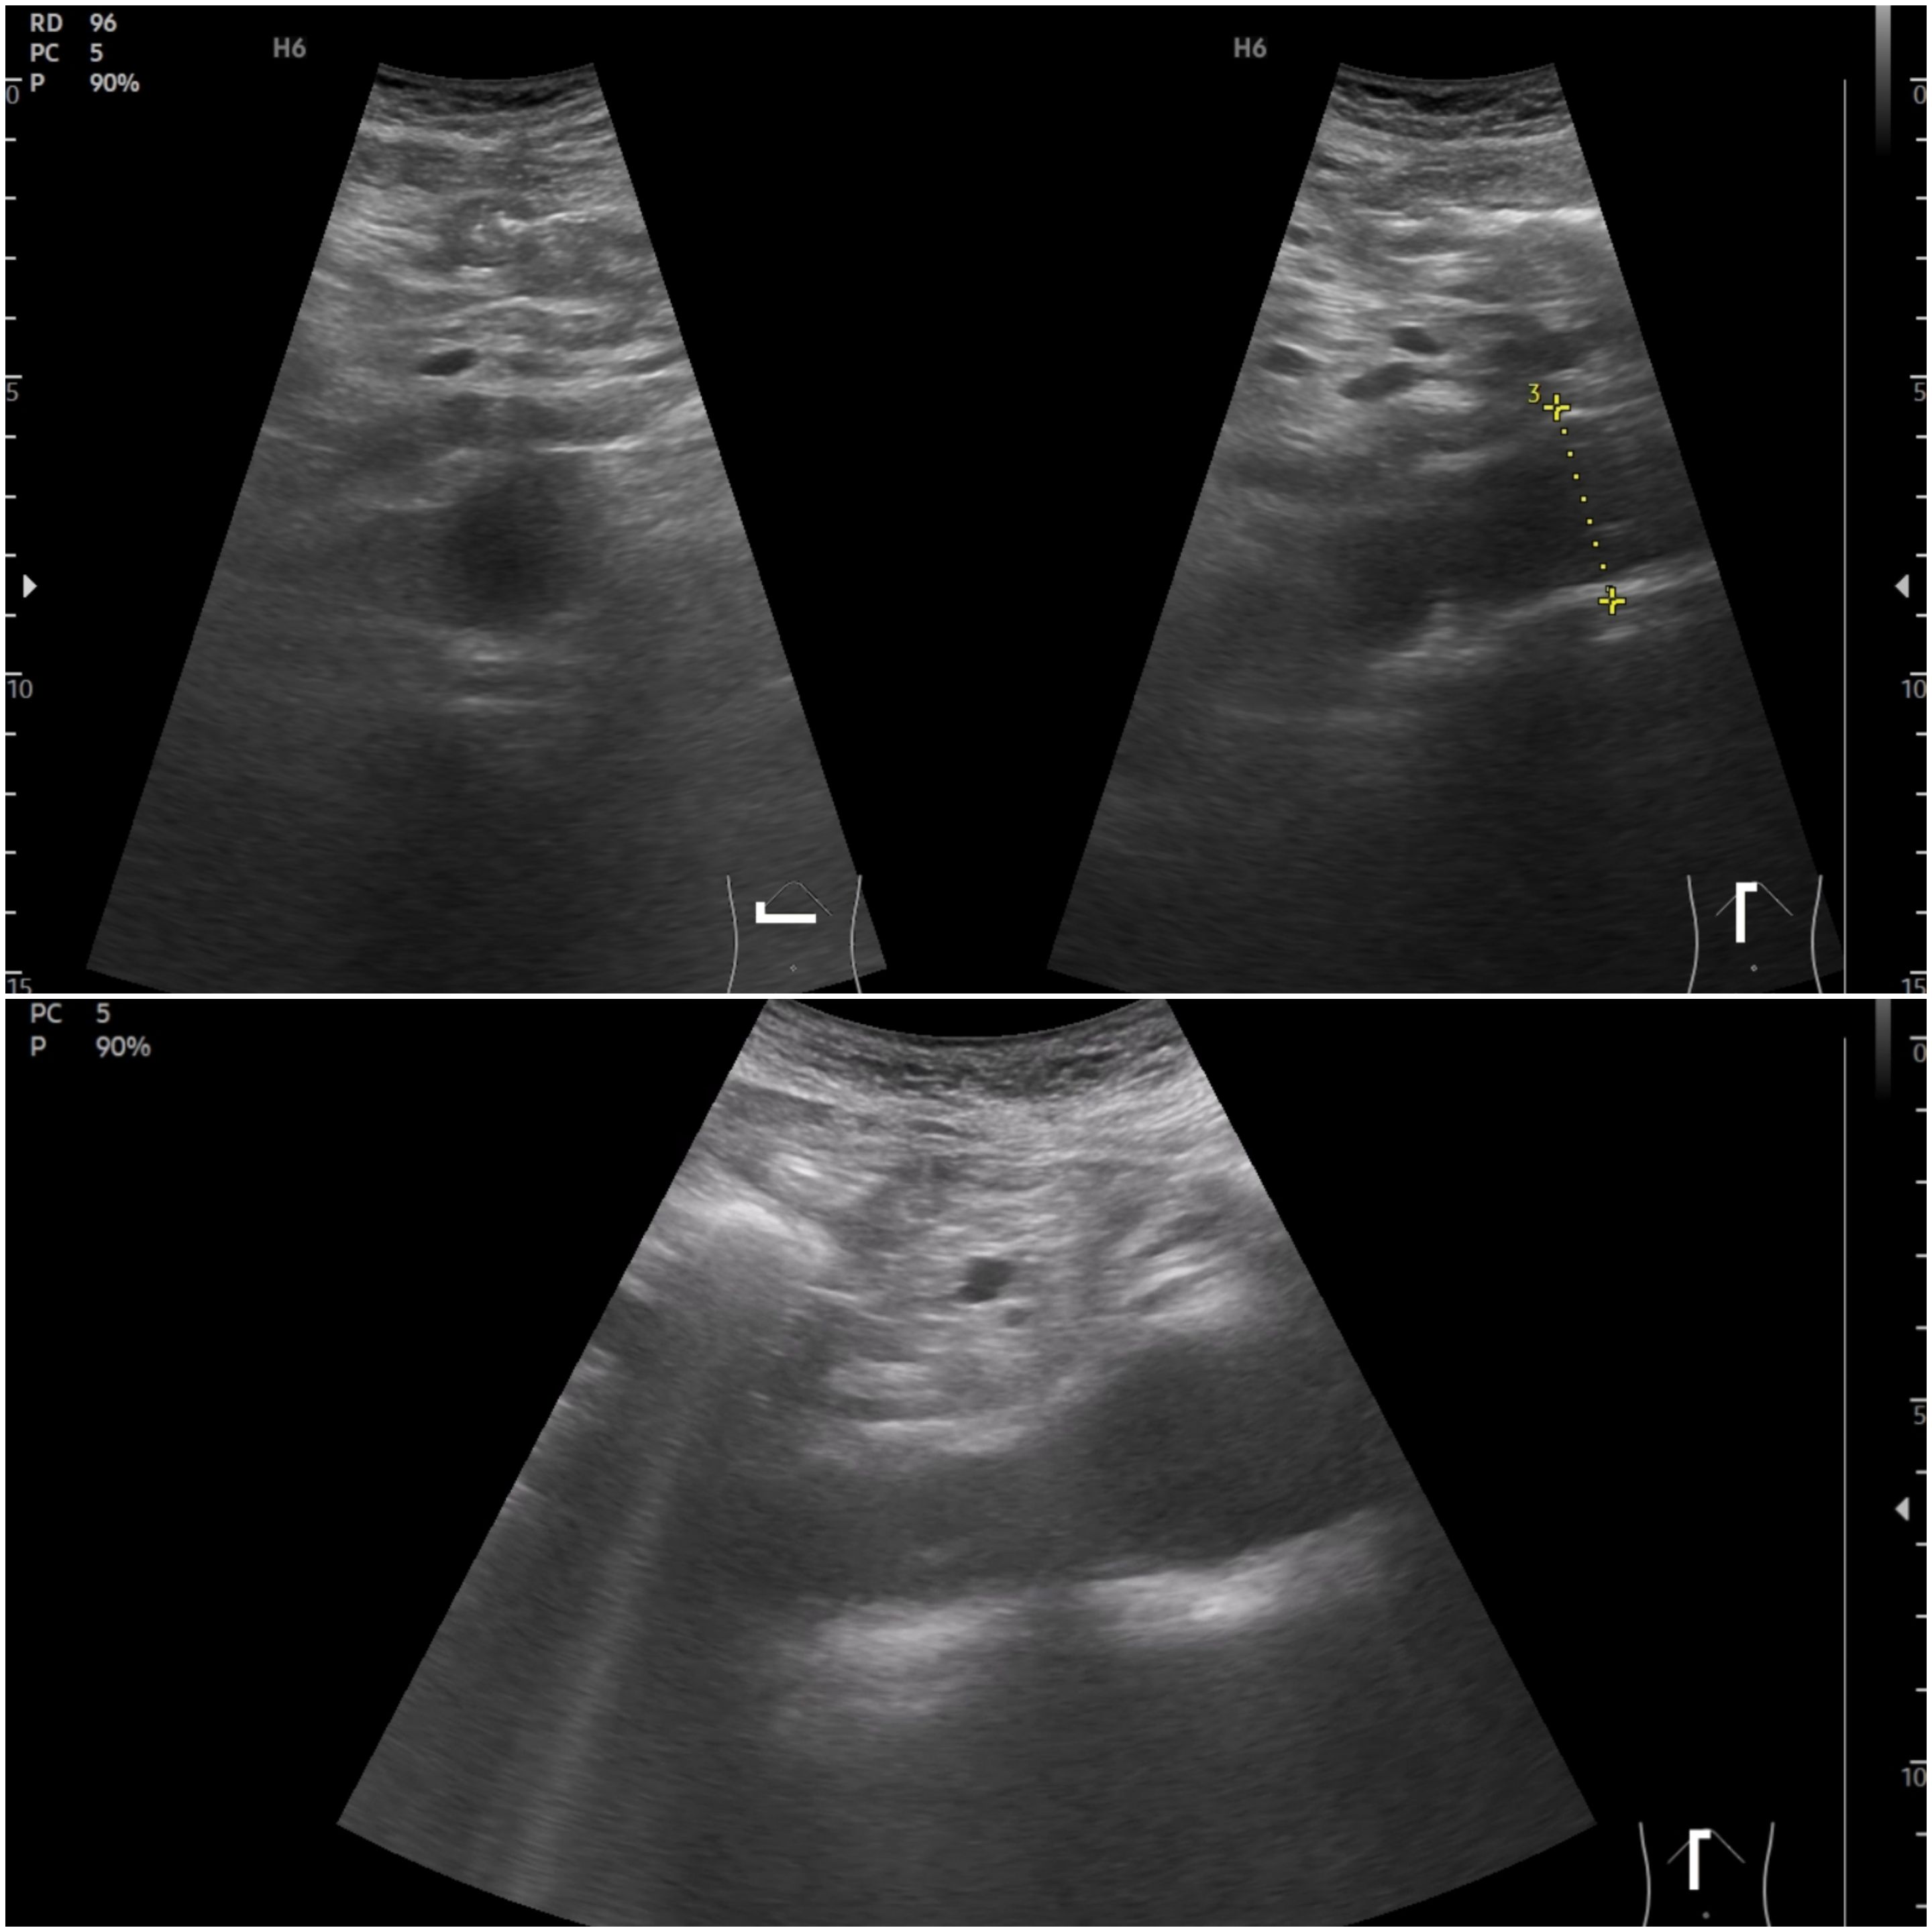

Ecografía: Próstata de 25 cc, sin lesiones intravesicales. Riñones de tamaño conservado con múltiples quistes bilaterales de varios tamaños, con criterios de quistes simples (anecoicos, pared fina, sin septos ni componente sólido, con refuerzo posterior), en número de más de cinco por cara riñón. Aorta abdominal de calibre aumentado a nivel epigastrio 35 mm llegando a 39 mm porción más distal. Aumento de calibre de ambas ilíacas.

Aneurisma aorta abdominal e ilíaco.

Hallazgo de aneurisma de aorta abdominal (AAA) en paciente con enfermedad arterial periférica y alto riesgo cardiovascular. El diferencial ecográfico incluye ectasia aórtica y sobrestimación por tortuosidad/planos oblicuos. Deben buscarse los signos de disección. Los quistes renales se clasifican como simples, diferenciándolos de quistes complejos y masas sólidas, pero en varón de 66 años siendo más de 5 en cada riñón obligan a pensar en la enfermedad poliquística.

Seguimiento periódico del AAA en Primaria, intensificación de los FRCV en especial la dislipemia en Prevención secundaria. Derivación a Nefrología.